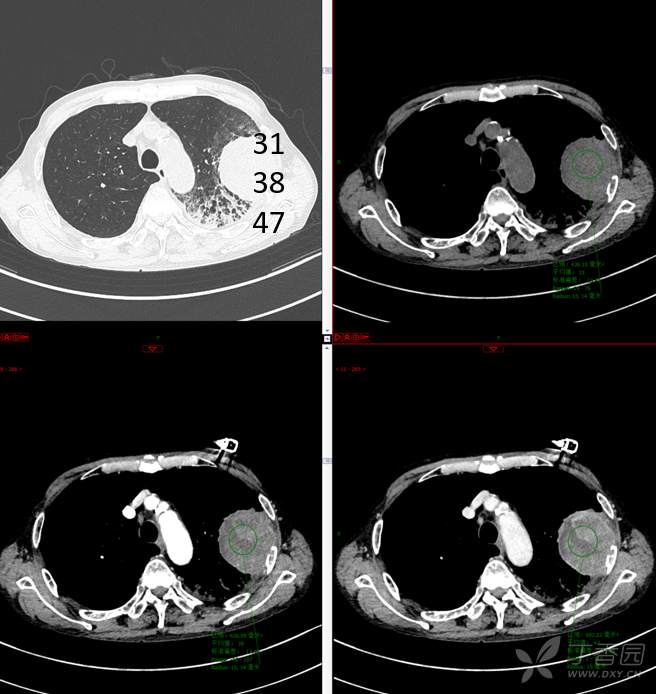

现病史:患者自诉5月前无明显原因及诱因出现纳差、乏力,伴进食后腹胀,无腹痛、腹泻、发热、盗汗、恶心、胸闷,未行特殊处理。1月前无明显原因诱因出现咳嗽,呈阵发性,咳白痰,痰中带鲜红色血丝,10余口/日,无血块,仍伴纳差、乏力、进食后腹胀,无恶心、呕吐、呕血,无头晕、心慌、喘憋、胸闷。在家未行特殊治疗,来我院就诊,2022.8.18行胸部(肺)CT平扫:左上肺占位并左侧肋骨骨质破坏,考虑间叶源性恶性肿瘤。门诊以“肺肿物”收入我科。患者自发病以来,神志清,精神可,饮食差,睡眠可,二便正常,近3月减轻5Kg。